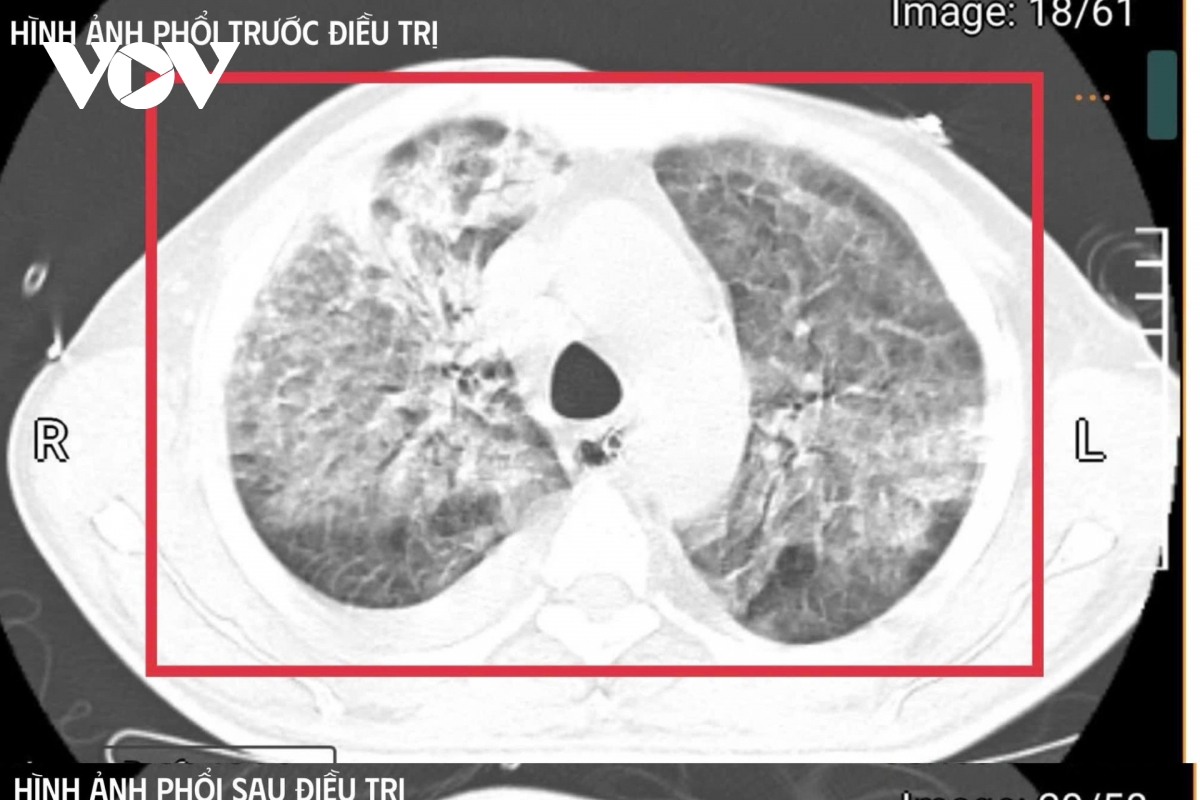

Hình ảnh phổi của bệnh nhân trước khi điều trị. (Ảnh: BVCC)